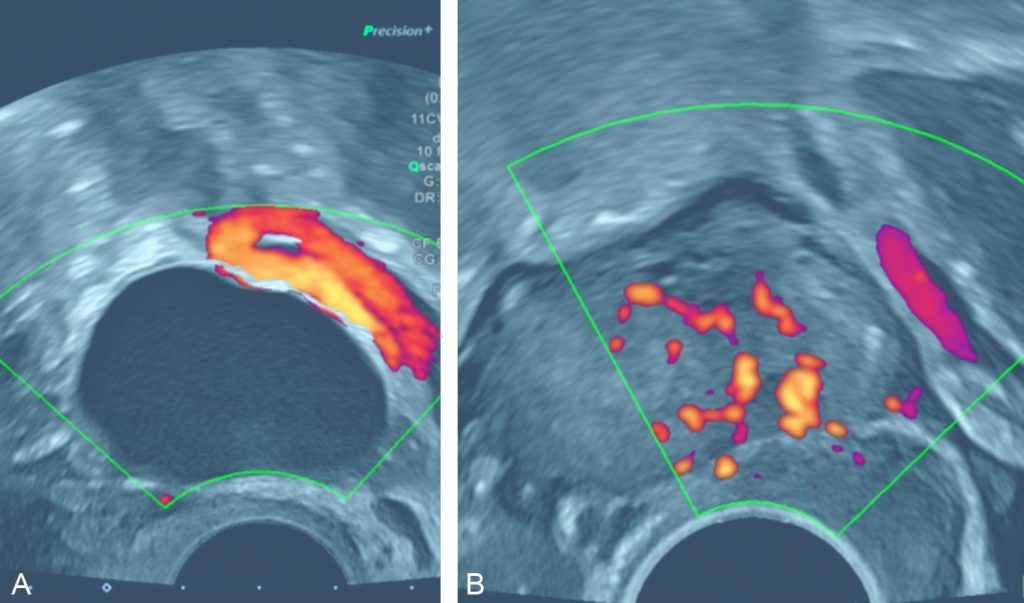

Un kyste fonctionnel (figure 20.10A) est en général une formation kystique uniloculaire pure ou plurilocaculaire avec une cloison fine, sans végétation, ni portion tissulaire intra- ou extrakystique, de paroi fine. Une hypervascularisation périphérique au doppler couleur est possible.

Fig. 20.10 A. Patiente de 45 ans présentant une douleur pelvienne latéralisée à gauche. B. Patiente de 21 ans, nulligeste, découverte fortuite d’une masse ovarienne sur l’échographie réalisée pour contrôle de la pose d’un dispositif utérin.

A. L’échographie endovaginale retrouve une formation kystique uniloculaire pure ovarienne gauche, de parois fines, sans portion tissulaire, ni hypervascularisation au doppler couleur. Le contrôle échographique réalisé à 3 mois ne met plus en évidence la formation kystique, ce qui confirme son caractère fonctionnel. B. L’échographie endovaginale met en évidence une formation hyperéchogène ovarienne gauche avec hypervascularisation au doppler couleur, témoignant d’une volumineuse portion tissulaire, en faveur d’un kyste organique.

Source : CERF, CNEBMN, 2022.

Un kyste organique (figure 20.10B) peut se présenter par une formation kystique uniloculaire pure persistante depuis plus de 3 mois. Un kyste organique doit être évoqué en première hypothèse lorsqu’il existe une végétation, une portion tissulaire ou encore si les cloisons sont épaisses et irrégulières.